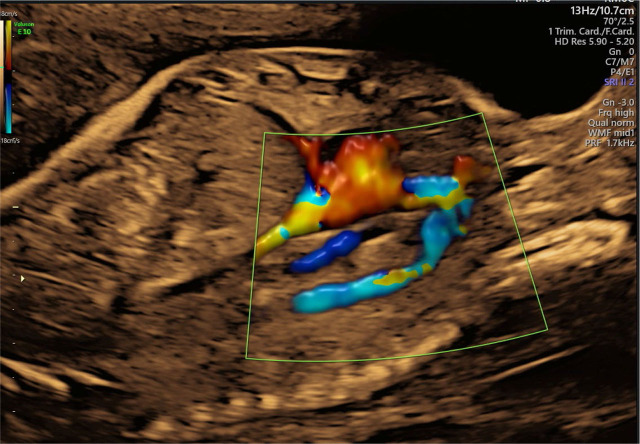

Total anomalous pulmonary venous connection is a rare congenital heart defect that can be diagnosed prenatally and might be very important for perinatal management. In addition to other cardiac abnormalities (levocardia, situs inversus, small left ventricle, double outlet right ventricle, parallel great vessels, and hypoplastic aortic arch), total anomalous pulmonary venous connection of a subdiaphragmatic type was diagnosed during a prenatal echocardiography examination in the second half of pregnancy. Fetal echocardiography monitoring showed no signs of congestive heart failure. The neonate was born at 38 weeks of gestation at our tertiary center. Postnatal echocardiography revealed significant progression in neonatal hemodynamics, and early cardiac surgery, involving repair of the pulmonary veins, pulmonary artery banding, and aortic arch reconstruction, was performed with a good outcome. This case is an excellent example of the value of prenatal echocardiography.

Abstract Image